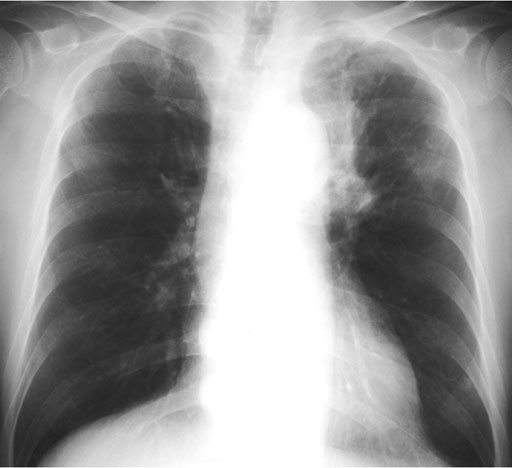

原発巣としては,肺癌,乳癌,大腸癌,腎癌,悪性黒色腫が多く,中でも肺癌が最も頻度が高く,扁平上皮癌,腺癌および他の組織型でも認められる.胃癌,食道癌,甲状腺癌,卵巣癌,喉頭癌,子宮頸癌,その他さまざまな血行性の遠隔転移が報告されている.本症例は筋肉腫瘤が初発症状で,初診時に胸部に異常は指摘できなかったが,術後1ヵ月後の胸部X線写真(図5)にて,左肺門上部の腫瘤影と左上葉の無気肺が認められた.

• 図5 胸部単純X線写真